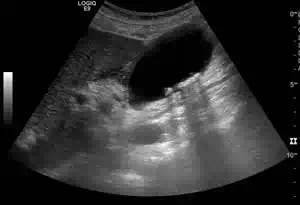

Längsschnitt über der Gallenblase

Die Abbildung zeigt eine verdickte und mehrschichtige Gallenblasenwand (akute Cholezystitis!). Im Lumen der Gallenblase erkennt man mehrere kleine Konkremente mit deutlichem dorsalen Schallschatten. Ein Artefakt, dass bei der Diagnose der Gallenblasenkonkremente hilfreich ist.

Pathologien der Gallenblase

Die Gallenblase ist deutlich wandverdickt und mehrschichtig. Die echoarmen (im Bild dunklen) Wandanteile sind Flüssigkeitseinlagerungen im Rahmen der akuten Cholezystitis